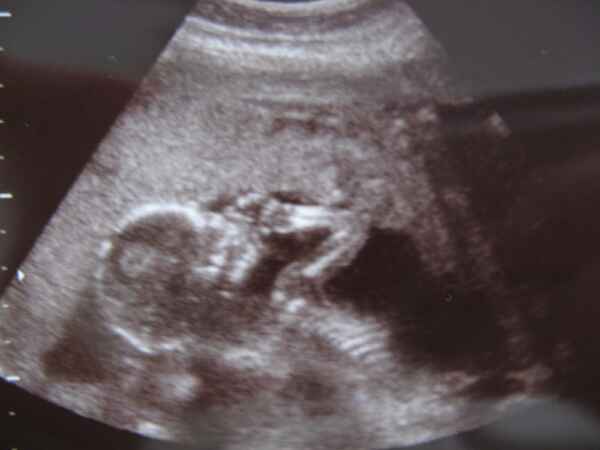

liza: szép a babó